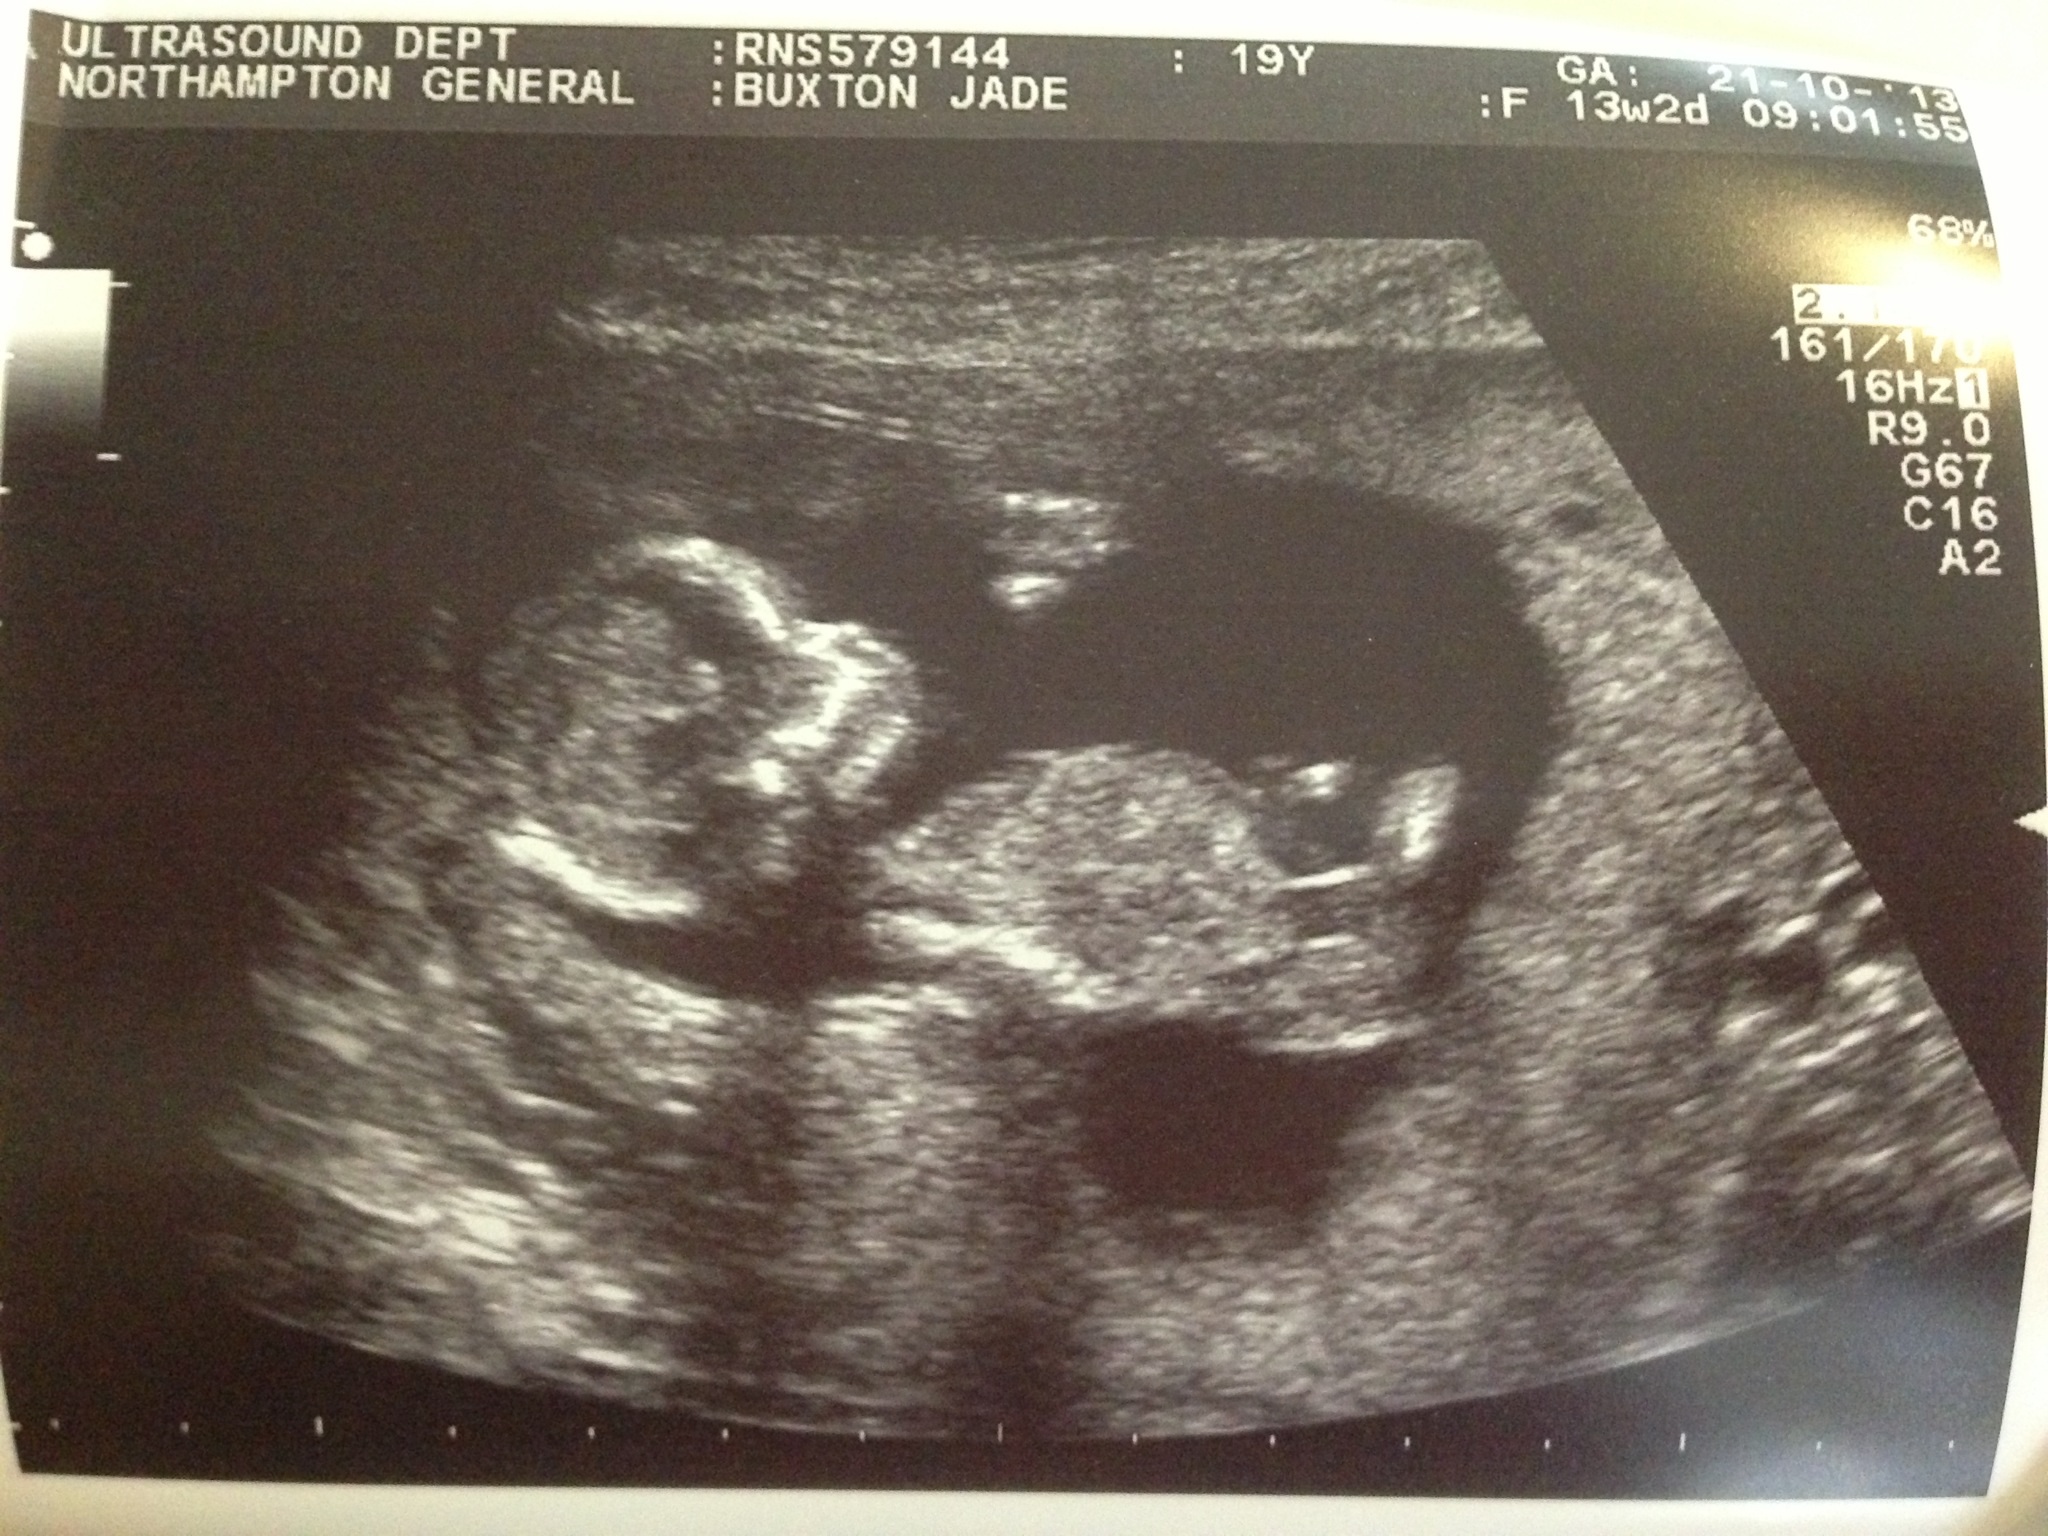

Attachment 15030Attachment 15031

Boy, I'd say

I'm not seeing any clues.

The skull looks more boy.